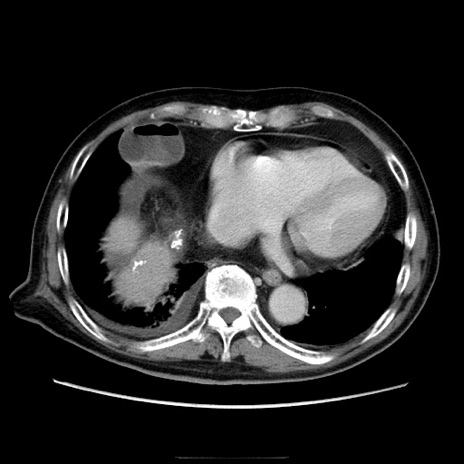

症例21(横断像)

【症例】70歳代男性

【主訴】腹痛

【現病歴】肝硬変・肝細胞癌にてかかりつけの方。約9時間前に食後より腹痛出現。症状が徐々に増悪し、嘔吐出現したため来院。

【既往歴】肝硬変、肝細胞癌(RFA、TACE後)

【身体所見】意識清明、表情苦悶様、BT 36℃、BP 129/78mmHg、P 88bpm、SpO2 97%(RA)、右上腹部から心窩部にかけて圧痛あり、反跳痛なし、筋性防御あり。

【データ】WBC 5800、CRP 0.16